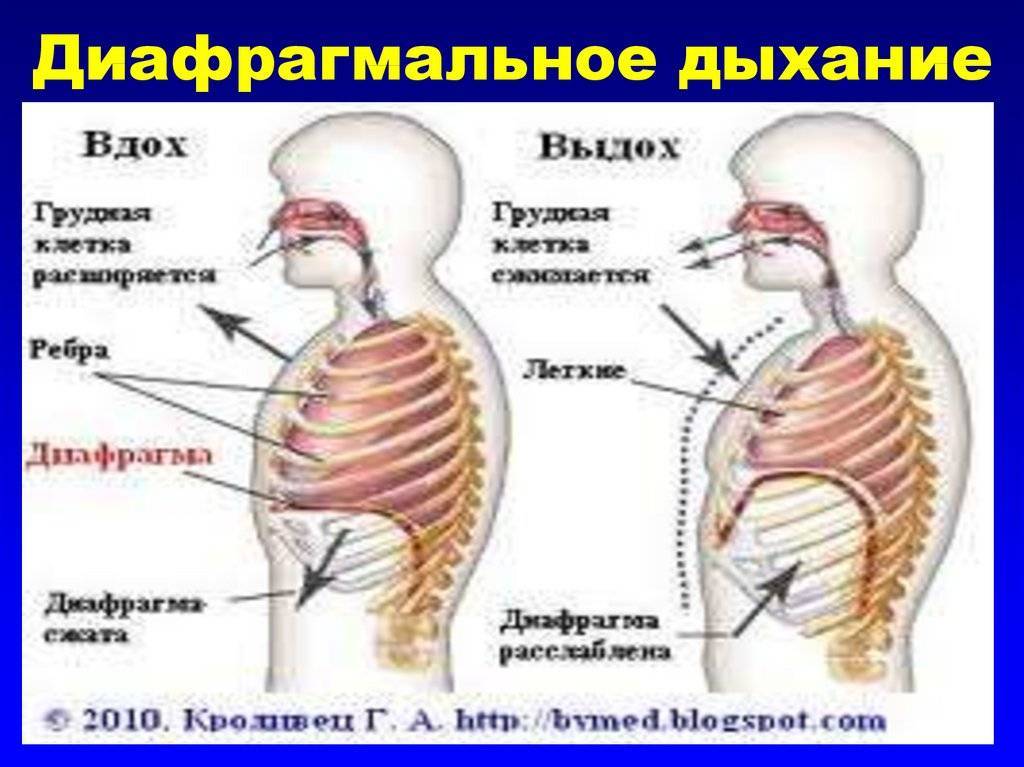

- Диафрагмальное (брюшное), когда в момент вдоха живот выступает вперёд, а на выдохе подтягивается по направлению к позвоночнику.

Главный орган в брюшном дыхании — диафрагма. Диафрагмальная мышца — это куполообразная перегородка, она отделяет грудную клетку от органов, расположенных ниже в брюшной полости. На вдохе диафрагмальная мышца идёт вниз и сжимается, заставляя брюшную стенку выдвигаться вперёд. В момент выдоха диафрагмальная мышца возвращается вверх и приобретает форму купола, выгоняя воздух из лёгких.